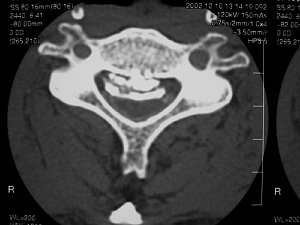

難病の頚椎後縦靱帯骨化症の手術前 |

手術後 | ||